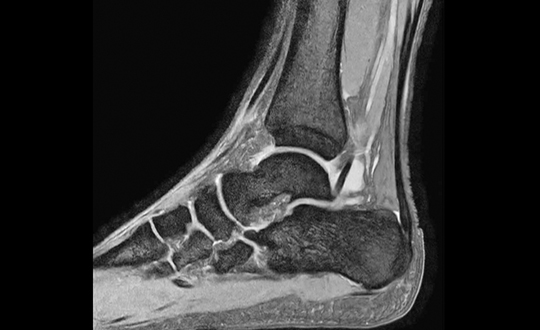

地域の先生方との連携をより強化すべく、最新の検査機器を導入しました。高精度かつ短時間での撮影を実現し、患者様の負担を軽減しながら、より明瞭な画像診断が可能となります。日常的な整形外科疾患から、より専門的な評価が必要な症例まで、地域の診療に役立つ検査体制を整えています。

高速・高精細撮影により短時間で体内を詳しく撮影できるCT装置。80列検出器による高速撮影とAIDR 3D Enhanced技術で被ばくを低減し、安全性と精度の高い検査を行います。

デジタル技術により高画質と低被ばくを両立したレントゲン装置。ISS方式の自動撮影条件設定や長尺撮影に対応し、全脊椎・全下肢の一括撮影も可能。短時間で体への負担が少ない検査を行います。

関節疾患、スポーツ障害、骨折など、幅広い症例に対応可能で、患者様一人ひとりに合わせた治療方針を提案しています。術前検査から術後フォローまで一貫した対応が可能であり、地域の先生方との連携のもと、必要な症例に対し迅速かつ的確に対応します。